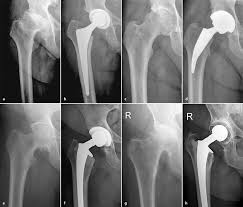

Huftgelenkersatz Klinikum Aschaffenburg Alzenau

Huftprothese Kunstliches Huftgelenk Sportopaedie Heidelberg